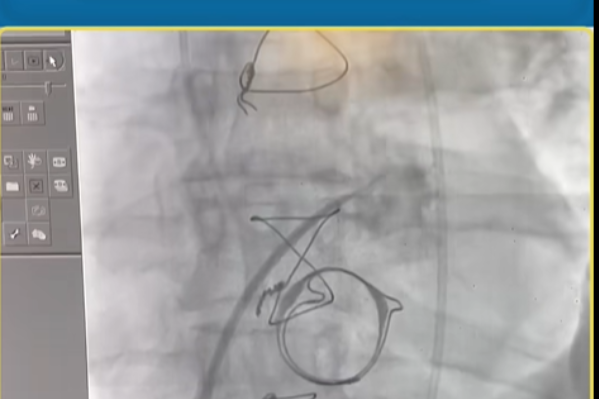

في إنجاز طبي يُعد الأول من نوعه في بلادنا ويمثل نقلة نوعية في مجال القلب والقسطرة القلبية، نجح فريق المستشفى الأوروبي الحديث بقيادة الأستاذ الدكتور طه الميموني – استشاري أول طب القلب والقسطرة القلبية وتداخلاتها – في إجراء عملية دقيقة لتركيب صمام قلب عبر القسطرة (TAVI)، وهو إجراء يُغني عن عملية القلب المفتوح التي تُعد أكثر تعقيدًا وتحمل مخاطر عالية وتتطلب فترة تعافي أطول.

إجراء TAVI هو تقنية حديثة ومتقدمة يتم فيها إدخال الصمام الجديد عبر القسطرة دون الحاجة إلى شق الصدر أو إيقاف عمل القلب، مما يجعل العملية أقل خطورة وأكثر أمانًا لمرضى القلب خصوصًا كبار السن أو المرضى الذين لا يتحملون الجراحة المفتوحة.

خرج المريض من المستشفى في اليوم التالي للعملية وهو بحالة صحية جيدة – في قصة نجاح تؤكد أن المستشفى الأوروبي الحديث هو بوابة الأمل لمرضى القلب في اليمن.